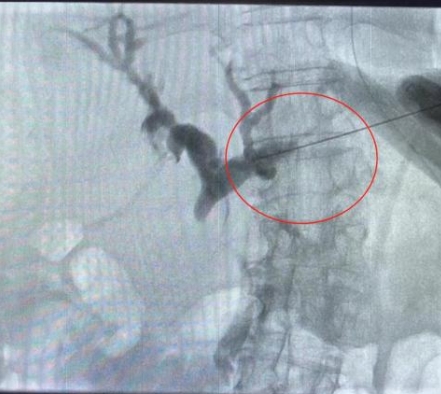

由于患者肝右葉占位巨大,完全遮擋右側(cè)穿刺路徑,左肝管為唯一穿刺路徑。介入科彭鵬醫(yī)生與重癥醫(yī)學(xué)科討論后,征得患者家屬同意后,擬行左側(cè)經(jīng)皮肝內(nèi)膽管穿刺引流術(shù)。術(shù)中一針便成功進(jìn)入膽道系統(tǒng),導(dǎo)絲引流管放置順利,造影顯示膽道系統(tǒng)顯影滿意,側(cè)孔位置可,引流順暢,37分鐘便結(jié)束了手術(shù),術(shù)后順利轉(zhuǎn)入普外科護(hù)理治療。這例手術(shù)的成功開展,刷新了該院介入團(tuán)隊(duì)高齡患者手術(shù)的新記錄!

經(jīng)皮肝內(nèi)膽管穿刺引流術(shù)是在醫(yī)學(xué)影像的引導(dǎo)下,利用穿刺針經(jīng)皮穿入肝內(nèi)膽管,注入對(duì)比劑,使肝內(nèi)外膽管迅速顯影后,置管引流以緩解梗阻癥狀。對(duì)于惡性梗阻性黃疸患者,通過該方式可降低血清膽紅素,有助于恢復(fù)肝腎功能,提高其生存質(zhì)量,延長生存期,部分患者還可獲得進(jìn)一步治療的機(jī)會(huì)。對(duì)于良性梗阻性黃疸患者,除有利于迅速緩解黃疸和感染等癥狀外,還可為后續(xù)治療提供通道。